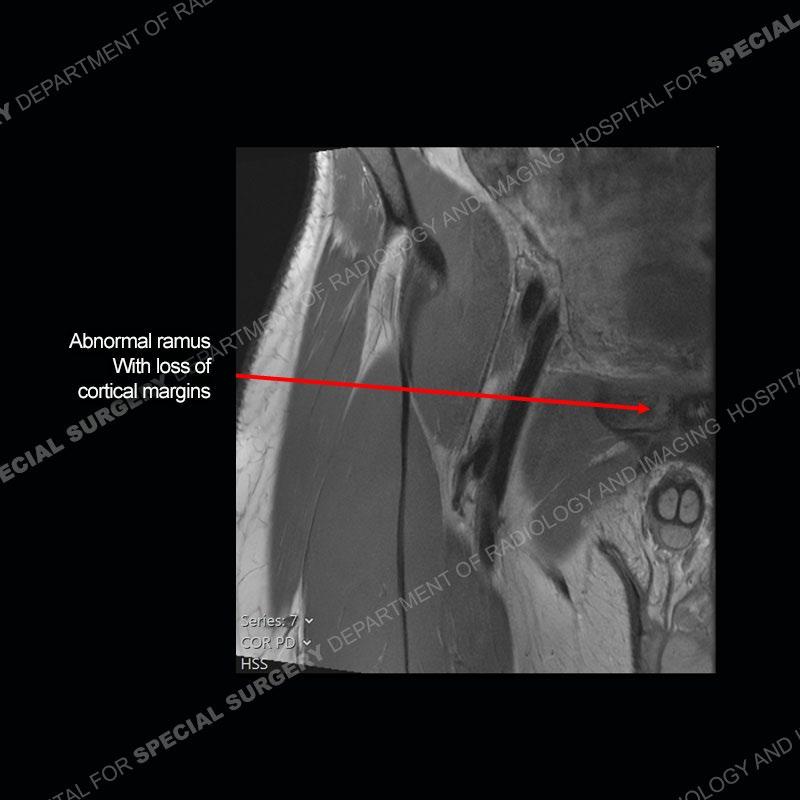

Radiographs did not demonstrate any clear abnormality. The MRI shows markedly abnormal signal of the right superior pubic ramus and abnormal signal/”mass” extending into the adjacent soft tissue. The inferior articular surface of the ramus showed what was thought to be bony destruction. CT examination shows a destructive process of the right superior pubic ramus.

This case was a bit surprising to all involved given that the young man is otherwise in good health and extremely active in sports. The original thought was this case was going to be an overuse injury or stress fracture. The pubic ramus with the adjacent physis acts as a metaphyseal equivalent and although not frequently thought of would be a reasonable location for infection/osteomyelitis. The first MRI was somewhat confusing as the process did not have an appearance of a stress injury or rectus adductor aponeurosis injury. The degree of edema of the bone and soft tissue together would be odd especially for a sports hernia process. Initially, the thought was of an aggressive process which could be infection or neoplastic. Particularly, the abnormal architecture of the inferior surface of the ramus looked like a destructive process.

The repeat MRI, with the marked degree of increased abnormality of the bone and soft tissue shifted the diagnosis to a high degree towards infection. Even the most aggressive of neoplasms would not have that the degree of change in a 3-day time span. The CT study was shown before the repeat MRI but actually occurred just after the repeat MRI. It helped confirm the destructive process of the ramus and particularly the abnormal architecture along the inferior margin. The patient went on to have a CT guided aspiration of one of the soft tissue collections with 4cc of purulent fluid obtained. A surgical irrigation and debridement of the bone and soft tissue was performed. A PICC line was placed and the patient is currently undergoing IV antibiotic treatment with a possible repeat irrigation and debridement.